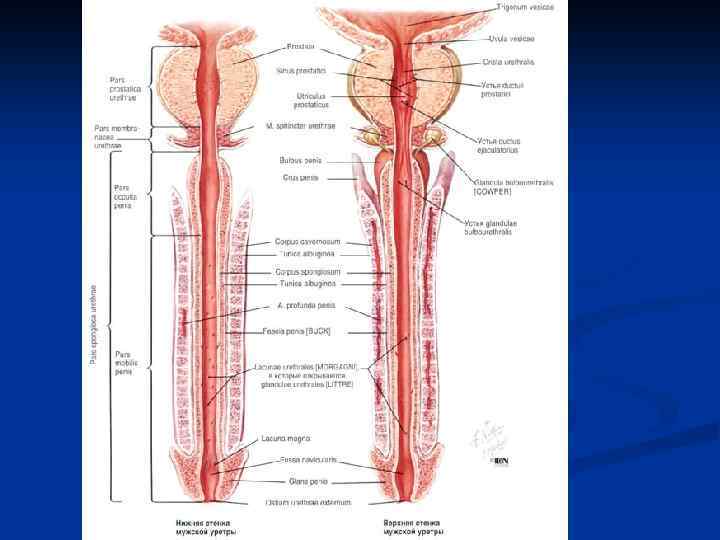

Путь выведения спермы: 1. Извитые семенные канальцы (700 -900) 2. Прямые семенные канальцы (250 -300) 3. Сеть яичка 4. Выносящие канальцы яичка (12 -15) 5. Проток придатка яичка 6. Семявыносящий проток (4 части – яичковая, канатиковая, паховая и тазовая) 7. Ампула семявыносящего протока + выделительный проток семенного пузырька 8. Семявыбрасывающий проток 9. Мужская уретра

Путь выведения спермы: 1. Извитые семенные канальцы (700 -900) 2. Прямые семенные канальцы (250 -300) 3. Сеть яичка 4. Выносящие канальцы яичка (12 -15) 5. Проток придатка яичка 6. Семявыносящий проток (4 части – яичковая, канатиковая, паховая и тазовая) 7. Ампула семявыносящего протока + выделительный проток семенного пузырька 8. Семявыбрасывающий проток 9. Мужская уретра

1. 2. 3. 4. 5. 6. 7. 8. 9. Путь выведения спермы: Извитые семенные канальцы (700 -900) Прямые семенные канальцы (250 -300) Сеть яичка Выносящие канальцы яичка (12 -15) Проток придатка яичка Семявыносящий проток (4 части – яичковая, канатиковая, паховая и тазовая) Ампула семявыносящего протока + выделительный проток семенного пузырька Семявыбрасывающий проток Мужская уретра

1. 2. 3. 4. 5. 6. 7. 8. 9. Путь выведения спермы: Извитые семенные канальцы (700 -900) Прямые семенные канальцы (250 -300) Сеть яичка Выносящие канальцы яичка (12 -15) Проток придатка яичка Семявыносящий проток (4 части – яичковая, канатиковая, паховая и тазовая) Ампула семявыносящего протока + выделительный проток семенного пузырька Семявыбрасывающий проток Мужская уретра